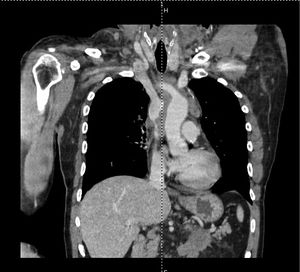

- CT with IV contrast

- Recommended imaging modality (assesses patency of the SVC, evaluate etiology mass vs. thrombus)